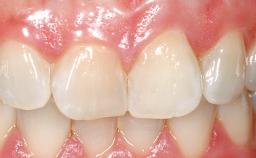

Immediate Placement of an Implant in a Maxillary Right Central Incisor Site

A 30-year-old female patient was referred to the office for the treatment of tooth 11. Her chief concern at the initial visit was to inquire, “Why is my tooth pink?” Upon clinical examination, it was determined that tooth 11 had a previous history of trauma and that the clinical crown had become noticeably pink in color as a result of internal resorption. This diagnosis was confirmed radiographically, indicating a large radiolucency involving the central and distal portions of the clinical crown. It was determined that restoration of this tooth was not possible, and that extraction was indicated. The presence of a mid-line diastema, which the patient wanted to reproduce, directed the treatment plan for tooth replacement utilizing a dental implant.

Prosthesis Type FDP

SAC Level Advanced

Defining Characteristics One missing tooth to be replaced by an implant-borne crown

Esthetic Risk High